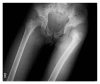

Traumatic dislocation of the hip in a child caused by trivial force for age

Traumatic hip dislocation in children has a relatively rare occurrence. There are some residual complications, such as avascular necrosis of the femoral head, growth disturbance caused by premature fusion, neurological injury, recurrent dislocation, and posttraumatic arthritis. There is no consensus in the literature about the period of non-weight bearing after reduction. A rare case of a 13-year-old boy of hip dislocation caused by trivial force for age is reported followed by review of the pediatric literatures with treatment recommendation.